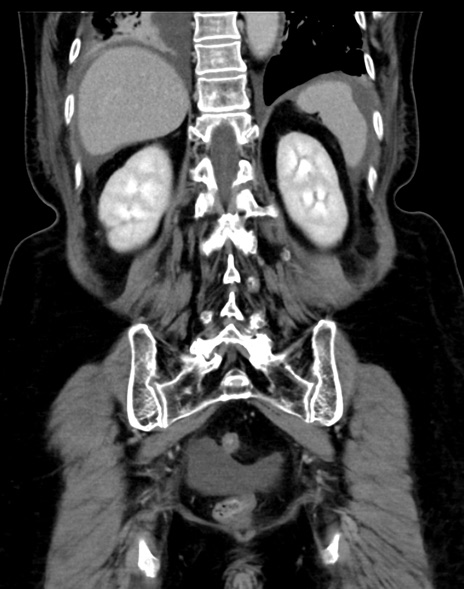

(横断像)1日半後